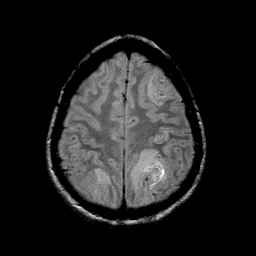

Sarcoma, MR Study #1 mr-pd -- Slice #19

[Home][Help][Clinical] Slice 19